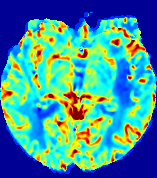

LesionRefer to captionRefer to captionRefer to captionRefer to captionRefer to captionRefer to caption𝐕rgbsubscript𝐕𝑟𝑔𝑏{\bf{V}}_{rgb}Refer to captionRefer to captionRefer to captionRefer to captionRefer to captionRefer to caption𝐕2subscriptnorm𝐕2{\|\bf{V}}\|_{2}Refer to captionRefer to captionRefer to captionRefer to captionRefer to captionRefer to captionRefer to caption3.53.53.52.82.82.82.12.12.11.41.41.40.70.70.70.00.00.0(mm/s)𝑚𝑚𝑠(mm/s)D𝐷DRefer to captionRefer to captionRefer to captionRefer to captionRefer to captionRefer to captionRefer to caption0.0200.0200.0200.0160.0160.0160.0120.0120.0120.0080.0080.0080.0040.0040.0040.0000.0000.000(mm2/s)𝑚superscript𝑚2𝑠(mm^{2}/s)Slice #1Slice #2Slice #3Slice #4Slice #5Slice #6

Figure 4: PIANO feature maps for another patient in the ISLES 2017 training set, where the lesion is located in the right hemisphere. Top row: segmented stroke lesion region (white) on different slices. The corresponding slices for the PIANO feature maps are shown in the following rows.

For a better insight into an estimated velocity field 𝐕𝐕{\bf{V}} and diffusion field 𝐃𝐃{\bf{D}}, we compute the following maps: (1) 𝐕rgbsubscript𝐕𝑟𝑔𝑏{\bf{V}}_{rgb}: Color-coded orientation map of 𝐕=(Vx,Vy,Vz)T𝐕superscriptsuperscript𝑉𝑥superscript𝑉𝑦superscript𝑉𝑧𝑇{\bf{V}}=(V^{x},V^{y},V^{z})^{T}, obtained by normalizing 𝐕𝐕{\bf{V}} to unit length and mapping its 3 components to red, green, blue respectively; (2) 𝐕2subscriptnorm𝐕2\|{\bf{V}}\|_{2}: 222 norm of 𝐕𝐕{\bf{V}}; (3) D𝐷D: scalar field in Eq. 5.

Fig. 3 and Fig. 4 show the PIANO feature maps estimated from two ISLES 2017 patients: all are highly consistent with the lesion in both cases. Details of the blood flow trajectories are revealed in 𝐕rgbsubscript𝐕𝑟𝑔𝑏{\bf{V}}_{rgb} by the ridged patterns and the sharp changes of colors in the unaffected (right) hemisphere, while the flat patterns appearing within the lesion provide little directional information about the velocity and indicate low velocity magnitudes. Velocity magnitudes are more directly visualized via 𝐕2subscriptnorm𝐕2\|{\bf{V}}\|_{2}, from which one can easily locate the lesion where 𝐕2subscriptnorm𝐕2\|{\bf{V}}\|_{2} is low. D𝐷D also indicates lower diffusion values in the lesion, though with less contrast potentially due to the fact that it captures the accumulated effect of CA diffusion at the voxel-level.